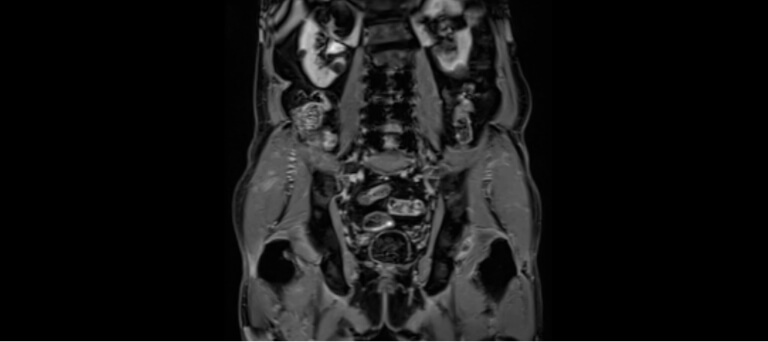

La resonancia magnética multiparamétrica (mpMRI) es una técnica de imagen avanzada, no invasiva, que permite visualizar la próstata con gran detalle y precisión.

Actualmente recomendada por guías internacionales en Estados Unidos y Reino Unido, esta prueba ayuda a identificar la presencia de lesiones con características sospechosas de cáncer, sin necesidad de procedimientos invasivos.

En nuestra Unidad Urológica contamos con esta tecnología, disponible en pocos centros en México, lo que nos permite ofrecer diagnósticos más precisos y personalizados para cada paciente.